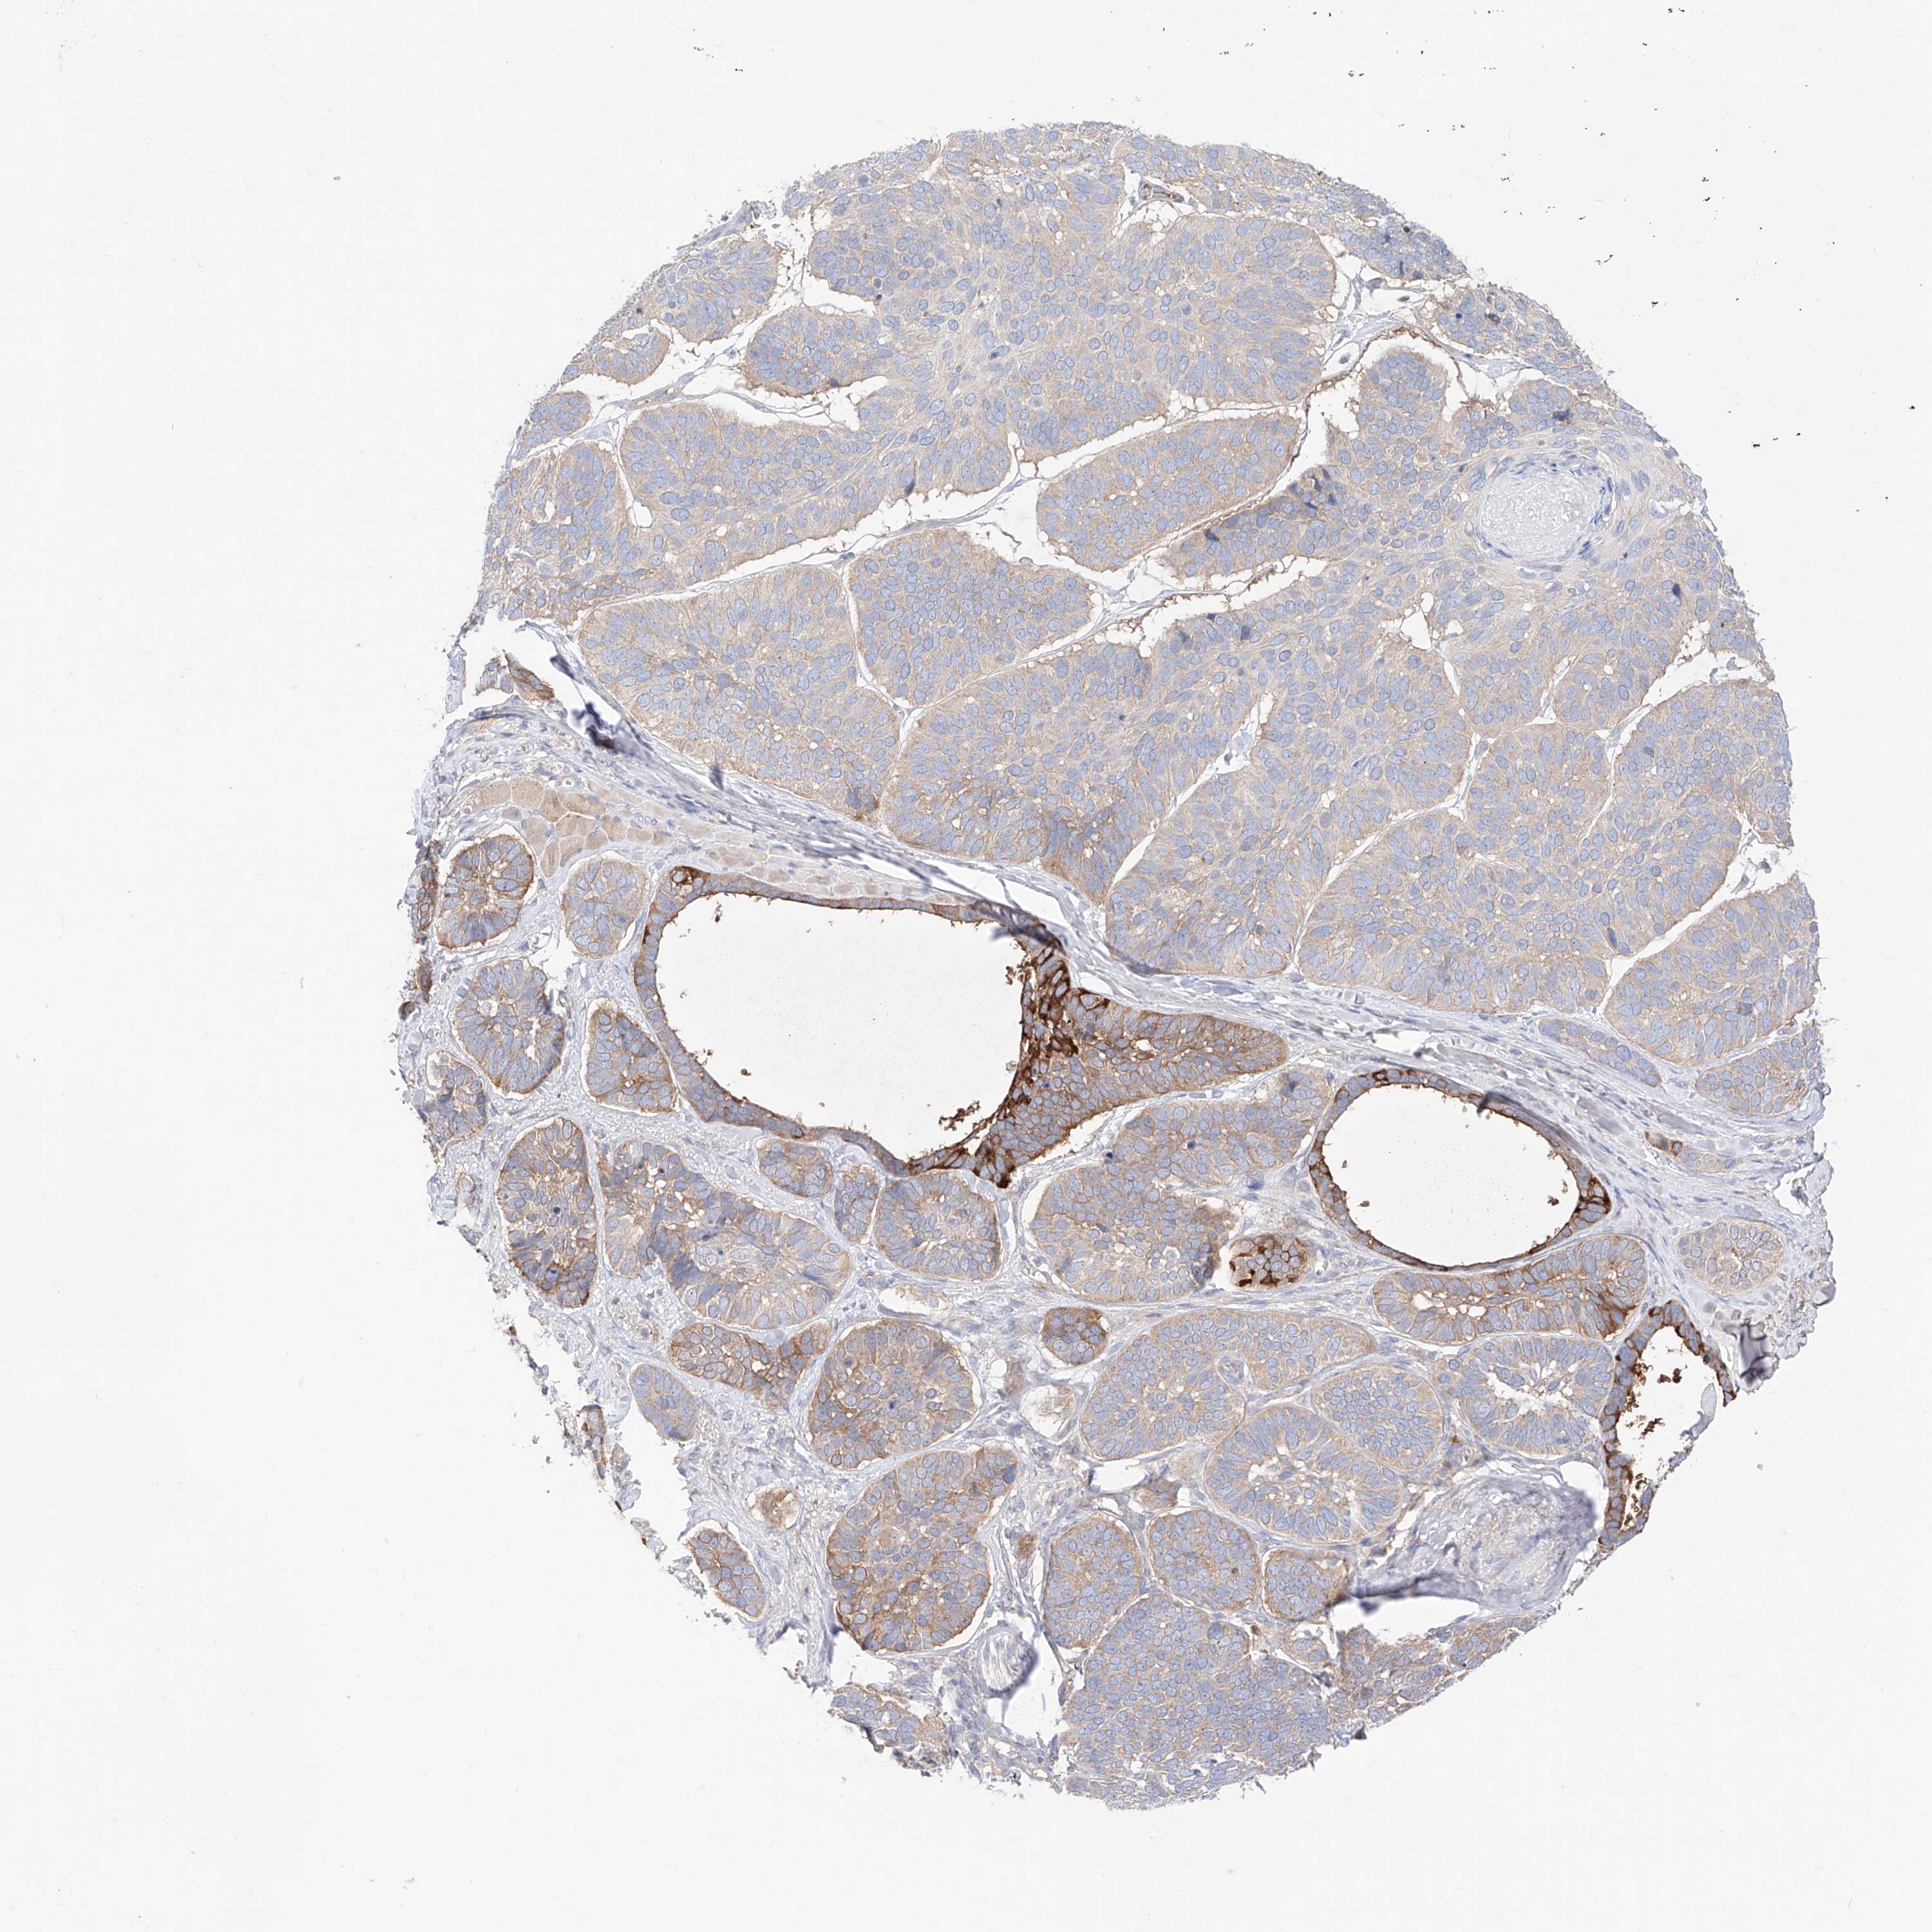

SKIN CANCER - Protein expressioni

A mouse-over function shows sample information and annotation data. Click on an image to view it in a full screen mode. Samples can be filtered based on level of antibody staining by selecting one or several of the following categories: high, medium, low and not detected. The assay and annotation is described here.

Antibody stainingi

Antibody staining in the annotated cell types in the current human tissue is reported as not detected, low, medium, or high, based on conventional immunohistochemistry profiling in selected tissues. This score is based on the combination of the staining intensity and fraction of stained cells.

Each image is clickable and will lead to virtual microscopy that enables deeper exploration of all samples and also displays staining intensity scores, fraction scores and subcellular localization as well as patient and tissue information for each sample.

Antibody HPA030646

Basal cell carcinoma